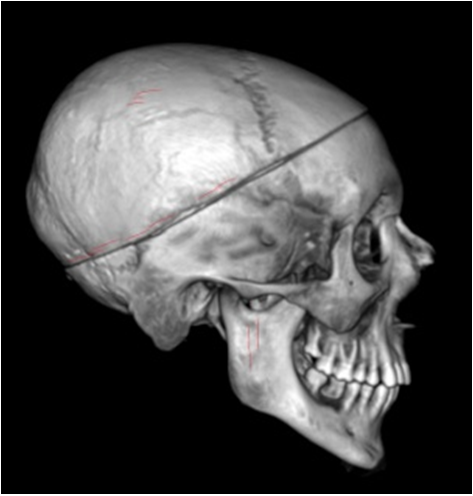

(à gauche) Scanner du crâne scié vu de profil droit de Thomas Craven montrant également les traces de découpe du cuir chevelu © I. Huyuh-Charlier, D. Hadjouis.